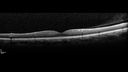

Left eye of patient with valsalva retinopathy in the right eye. Normal Examples Color, FA, OCT